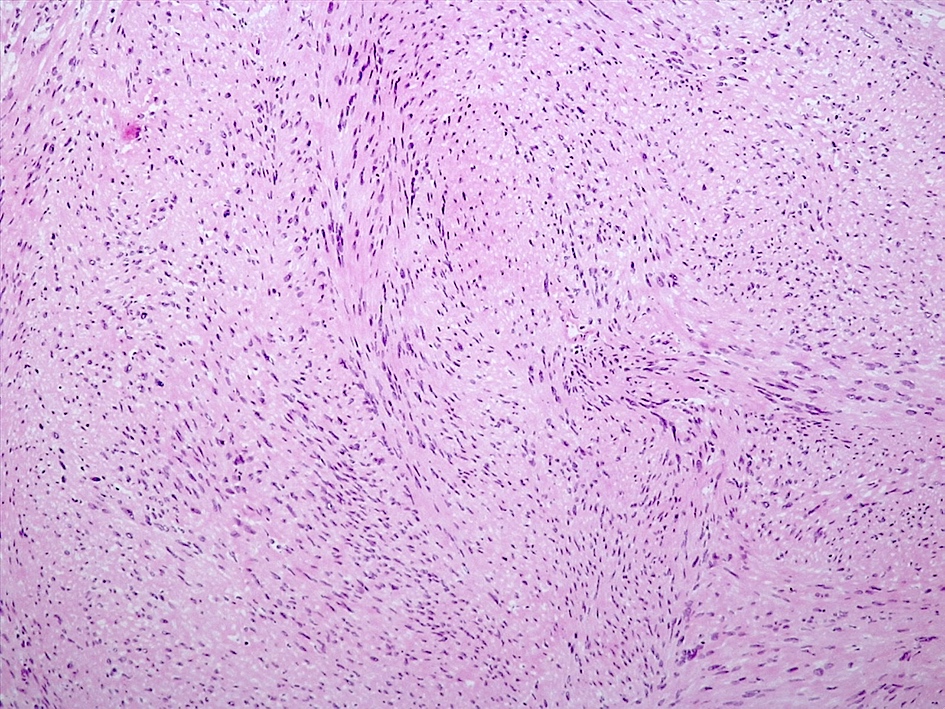

Microscopic (histologic) description

- Spindle cell tumor (usually biphasic) and composed of compact hypercellular areas (Antoni A tissue) showing nuclear palisading (Verocay bodies) and loose microcystic areas (Antoni B tissue) with collection of lipid laden histiocytes and thick walled hyalinized blood vessels (Surg Neurol Int 2020;11:454)

- Mitoses or focal degenerative atypia may be present

- Ancient subtype: characterized by scattered atypical or bizarre nuclei

Microscopic (histologic) images